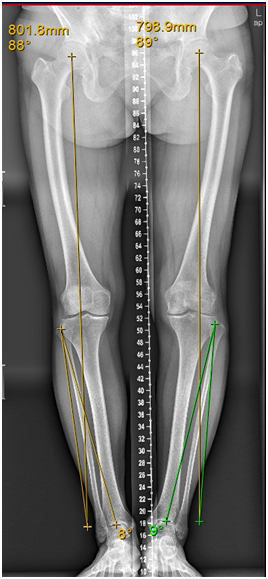

上图:黄色线是正常的力线位置,可明显看到此例患者的下肢力线位置异常

从生物力学来说,下肢力线就是“双腿的重力线”;从解剖学来看,下肢力线就是“下肢各器官的结构学连接线”。当下肢各个关节不处于正常的结构和位置,下肢力线出现异常时,不但双腿局部出现变形,从而导致膝关节疼痛症状。如果通过手术能够改变下肢的力线,从根本上消除其症状。